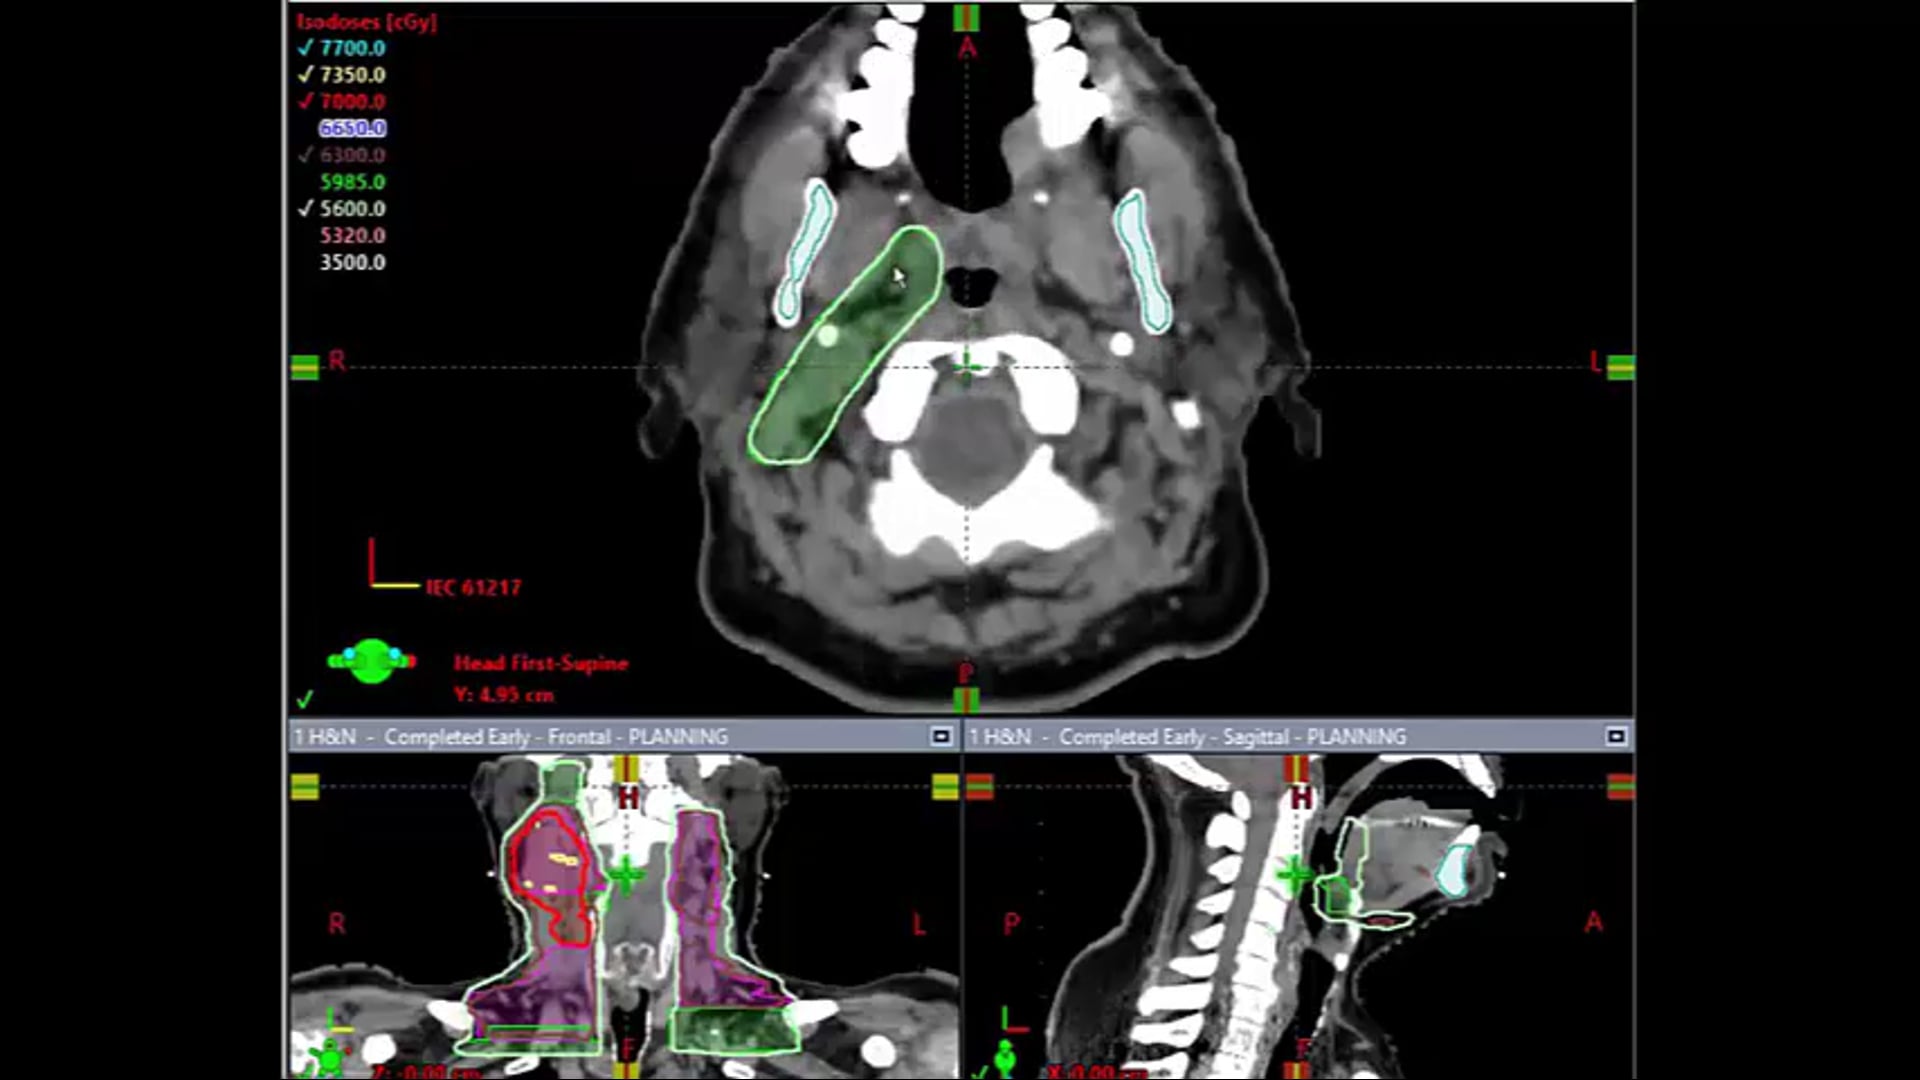

03/09/21- Dr. Kenneth Hu - Radiation Oncology - Head and Neck US

tongue-based cancer, dosimetry plan, treatment plan and contouring, contra-lateral node treatment, nasal pharynx treatment, bone invasive mass,